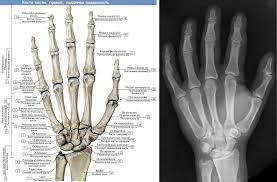

>>327929980

Аплазия пальцев правой кисти, я родилась такой.

тут как сказать - да, сравнить есть с чем, но все равно однозначно не скажешь. по функциям скорее как безымянный и средний наверное. но вообще, даже большой палец на правой руке не совсем и большой. он по другому выглядит и сгибается, один раз мне хирург даже сказал, что это как раз указательный палец.

родственники ничего такого не имеют. ноги тоже обычные.

Кто из черепашек ниндзя был твоим кумиром?

Пястные кости в кисти есть или их тоже только три?